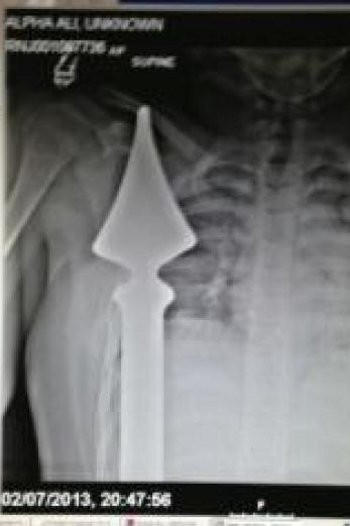

7. Dada Tertembus Besi Pagar Sekolah

|